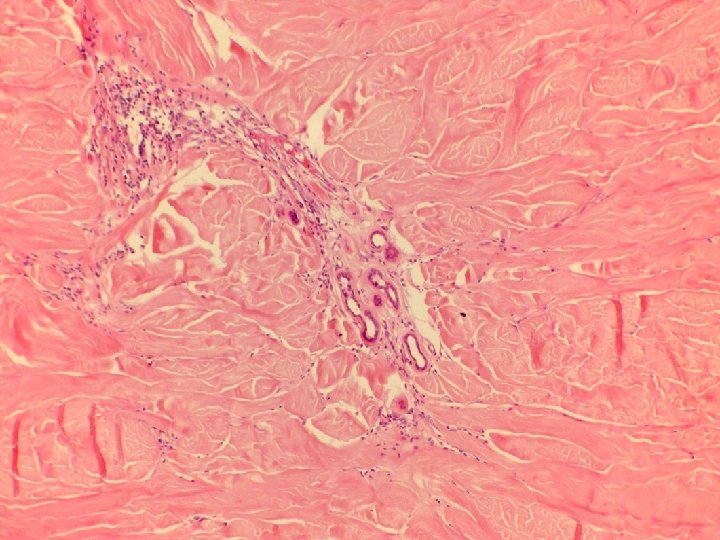

�Case number: 191 �Male aged 60 years. �Skin left popliteal fossa excision. Five week

�Case number: 191 �Male aged 60 years. �Skin left popliteal fossa excision. Five week history of nodule on skin. No pus. Has some insect bites. ? insect bite reaction, ? keratoacanthoma versus SCC. �Macro: Skin biopsy 18 x 13 x 2 mm in depth with a centrally raised slightly keatotic lesion 5 mm in diameter.